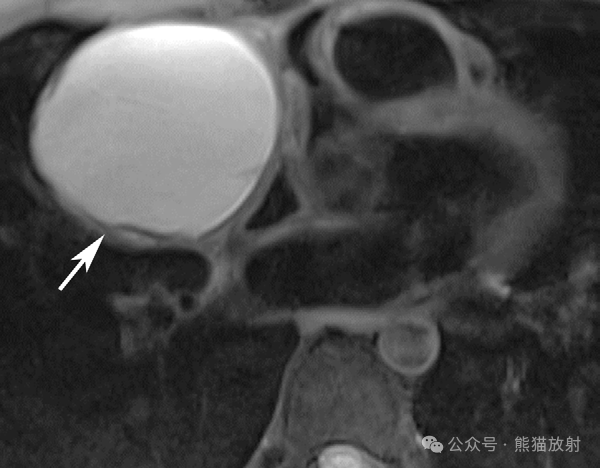

35岁男性,心包囊肿。胸部轴位T2WI显示右前心旁区域单房囊性病变(箭) ,无任何分隔或实性成分。